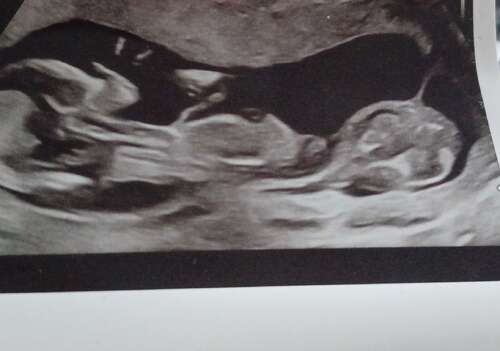

Bij week 8-10-13 heb en we een echo gehad. Wat bleek bij mij het geval dat ik dus een tweeling zou hebben gehad en had 1 hematoom in de placenta en dan het opruimen van het kleine vruchtzakje die niet bevrucht is.

Op de echo’s kon je duidelijk zien dat we twee zakjes hadden en inmiddels zou dat langzaam weg gaan.